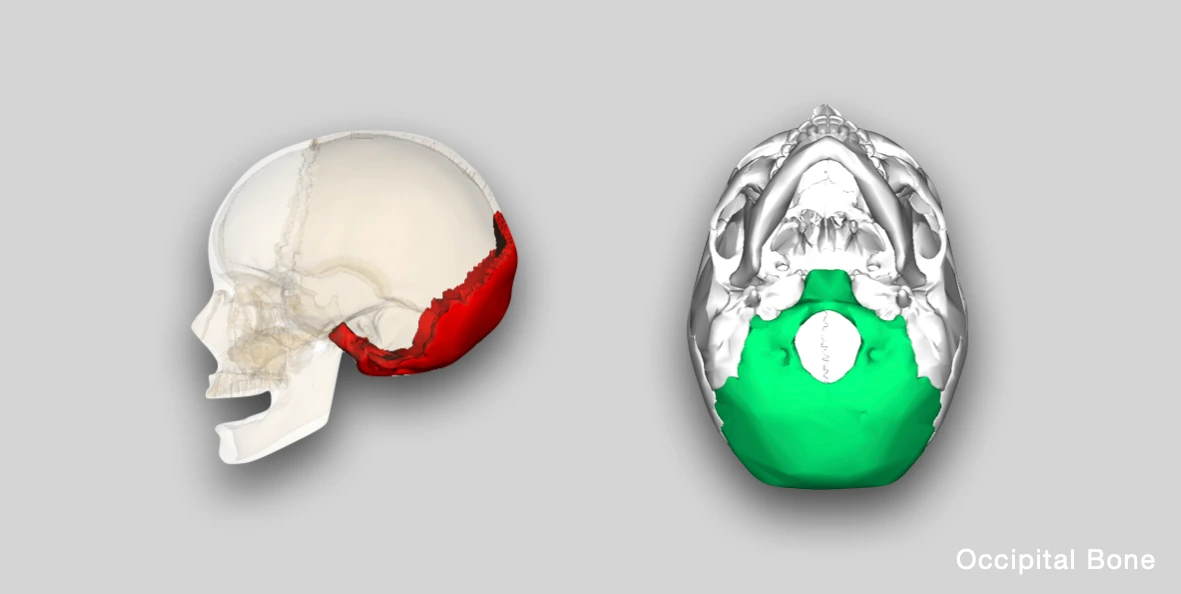

The occipital bone forms the posterior and inferior part of the skull. It consists of four parts i.e., one squamous, two condylar/lateral and one basilar part, arranged around a large opening called foramen magnum.

Anatomical Position

In the anatomical position, the occipital bone should be held with:

- the concave surface/fossae forwards,

- the condylar processes downwards, and,

- the basilar part anteriorly, with the inferior angle pointing upwards.

Source: en:Anatomography (Wikimedia Commons)

Source: en:Anatomography (Wikimedia Commons)